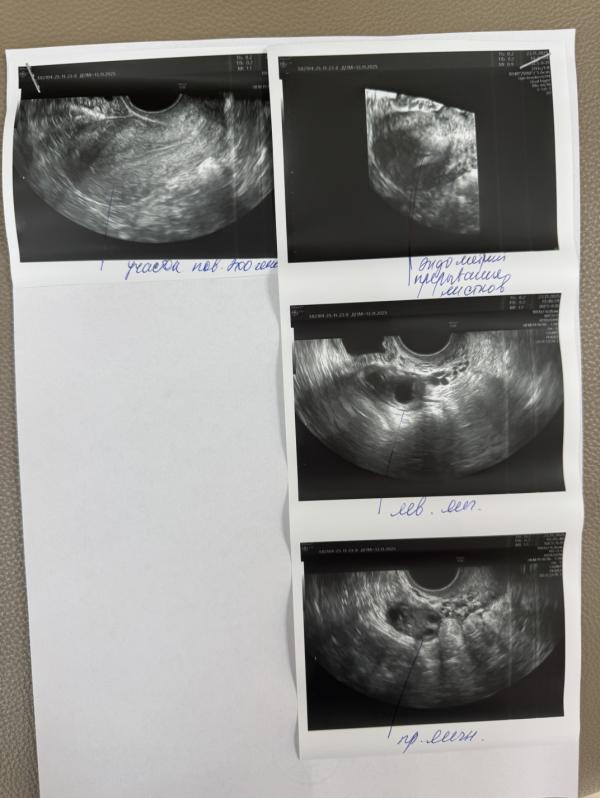

Вам надо на гистероскопию, синехии и полипы уберут.. сама недавно делала

У вас не однородный эндометрий это уже звоночек у меня так было на МРТ даже отправили не увидели полип только во время операции обнаружили и удалили

Мой вам совет. Прежде чем пойти на гистероскопии , а она вам понадобиться, пролечитесь, синехии просто так не появляются, значит было воспаление.

И планируйте сразу как можно, потому что синехии уже будут всегда возвращаться , к очень большому сожалению